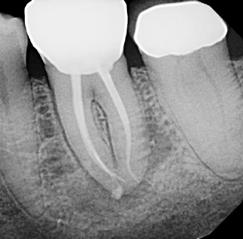

Due to the controlled memory, the files always follow the anatomy of the canal, thus significantly reducing the risk of ledging, transportation or perforation of a canal. Like stainless steel files, the HyFlex EDM files can be pre-bent.

This is a crucial advantage in extremely curved root canals to avoid the creation of steps.

Clinical Case by

Gianluca Fumei